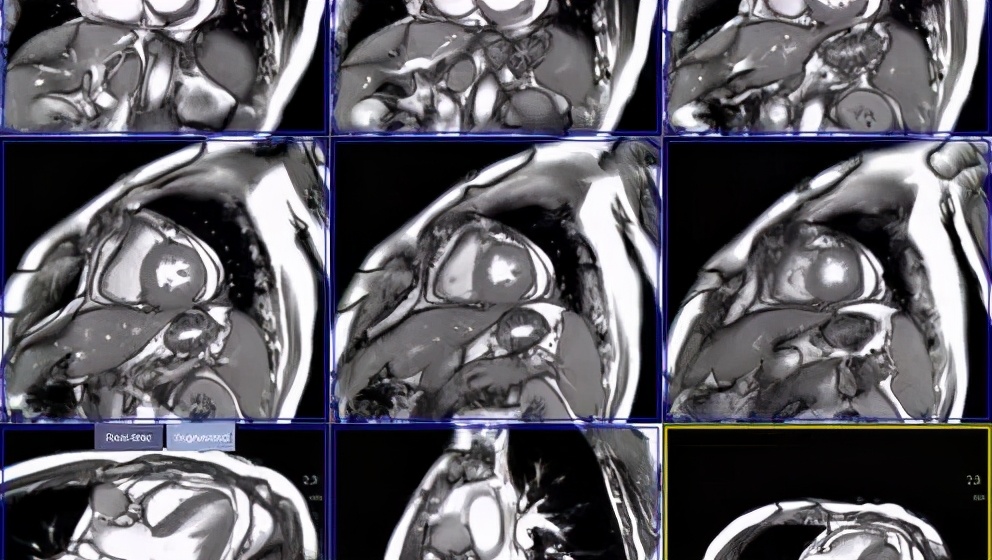

肿瘤心脏病学旨在最大程度地降低肿瘤患者心血管疾病的发病率和死亡率,其中强化早期评估、筛查与监测肿瘤患者心血管毒性,有助于改善患者的长期预后。抗肿瘤治疗过程中,心血管毒性的监测方法包括心电图、心脏影像学(心脏磁共振、心脏超声心动图、心脏放射性核素扫描)和生物标志物(肌钙蛋白、脑钠肽)。